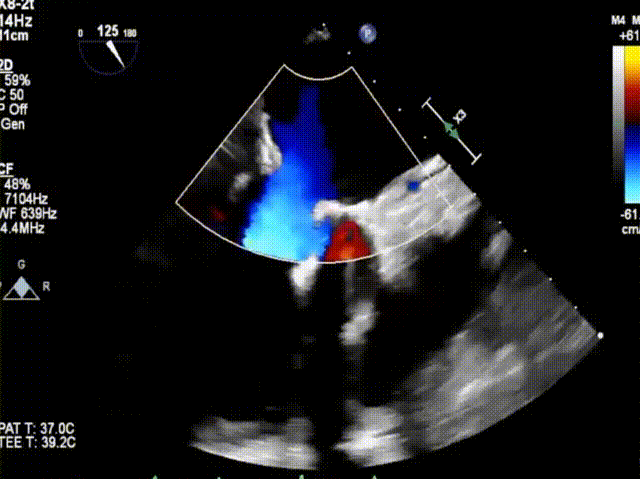

术后即刻超声评估

2021年12月22日,四川大学华西医院心脏内科陈茂、冯沅教授联合心脏外科蒙炜教授、麻醉科朱涛、陈果教授等组成的多学科团队完成了HighLife TSMVR技术的亚洲首例临床应用。手术过程顺利,人工瓣膜植入位置理想,术后即刻二尖瓣返流完全消失,无左室流出道梗阻,患者恢复良好。该例手术亦是亚洲地区开展的首例经房间隔二尖瓣置换术!

该例患者为74岁女性,因劳力性呼吸困难就诊,近期反复发作急性左心衰竭住院治疗,并伴有持续性房颤、高血压、糖尿病等疾病。超声心动图评估提示二尖瓣中重度返流、轻中度主动脉瓣返流与轻度三尖瓣返流,LVEDD 52mm,LVESD 40mm,LVEF 47%。二尖瓣返流机制为Carpentier I+IIIa型,有效返流口面积为0.31cm2,返流量47mL,瓣口面积为3.7cm2。因考虑外科手术风险高危,同时由于二尖瓣瓣口面积较小不适宜经导管二尖瓣缘对缘修复术,多学科团队讨论后决定使用Peijia HighLife TSMVR系统行经房间隔二尖瓣置换术。